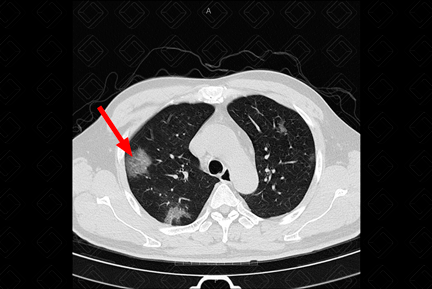

Descrição das figuras 1, 2 e 3: Tomografia computadorizada de tórax no momento da admissão. Esparsas opacidades em vidro fosco bilaterais, com envolvimento de mais de um lobo pulmonar e com distribuição predominantemente periférica. Em associação às áreas em vidro fosco, pode ocorrer ainda espessamento dos septos interlobulares, caracterizando o padrão de pavimentação em mosaico.

• Opacidades em vidro fosco, bilaterais, acometendo a maioria dos lobos pulmonares (acometimento multilobar), assimétricas e com predomínio na periferia dos pulmões;

• Em associação às áreas em vidro fosco, pode coexistir o espessamento dos septos interlobulares, caracterizando o padrão de pavimentação em mosaico;